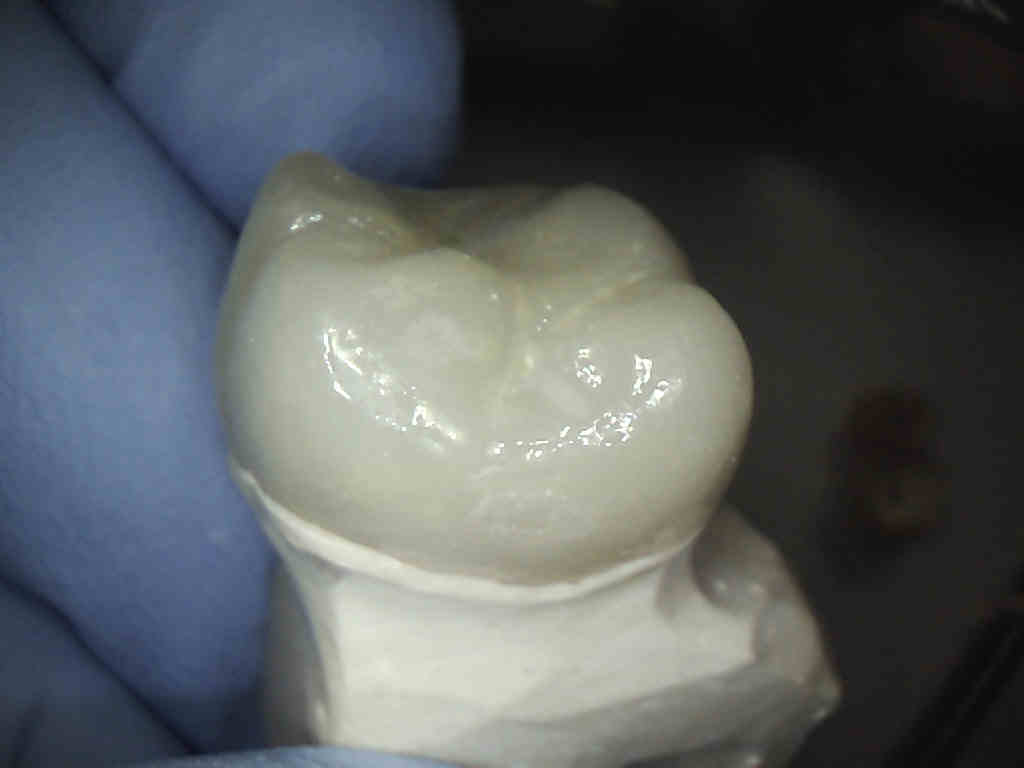

This is a picture of a final crown that will go over the newly treated root canal tooth.